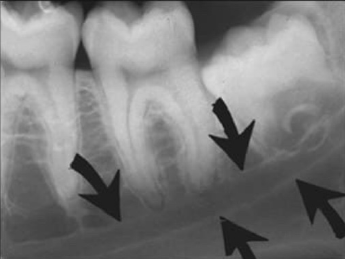

76. What is B showing?

Internal oblique ridge is the bony protuberance located on the lingual surface of mandible extending diagonally downward from the ramus and ending anteriorly near the apices of the premolars. Its function is to serve as an attachment site for the mylohyoid muscle of the floor of the mouth.

77. What is A showing?

36 / 40